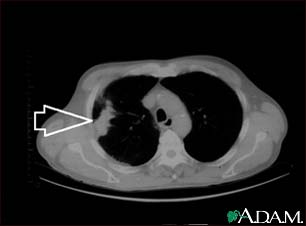

Lung mass, right lung - CT scan

This is a CT scan of the upper chest showing a mass in the right lung (seen on the left side of the picture).